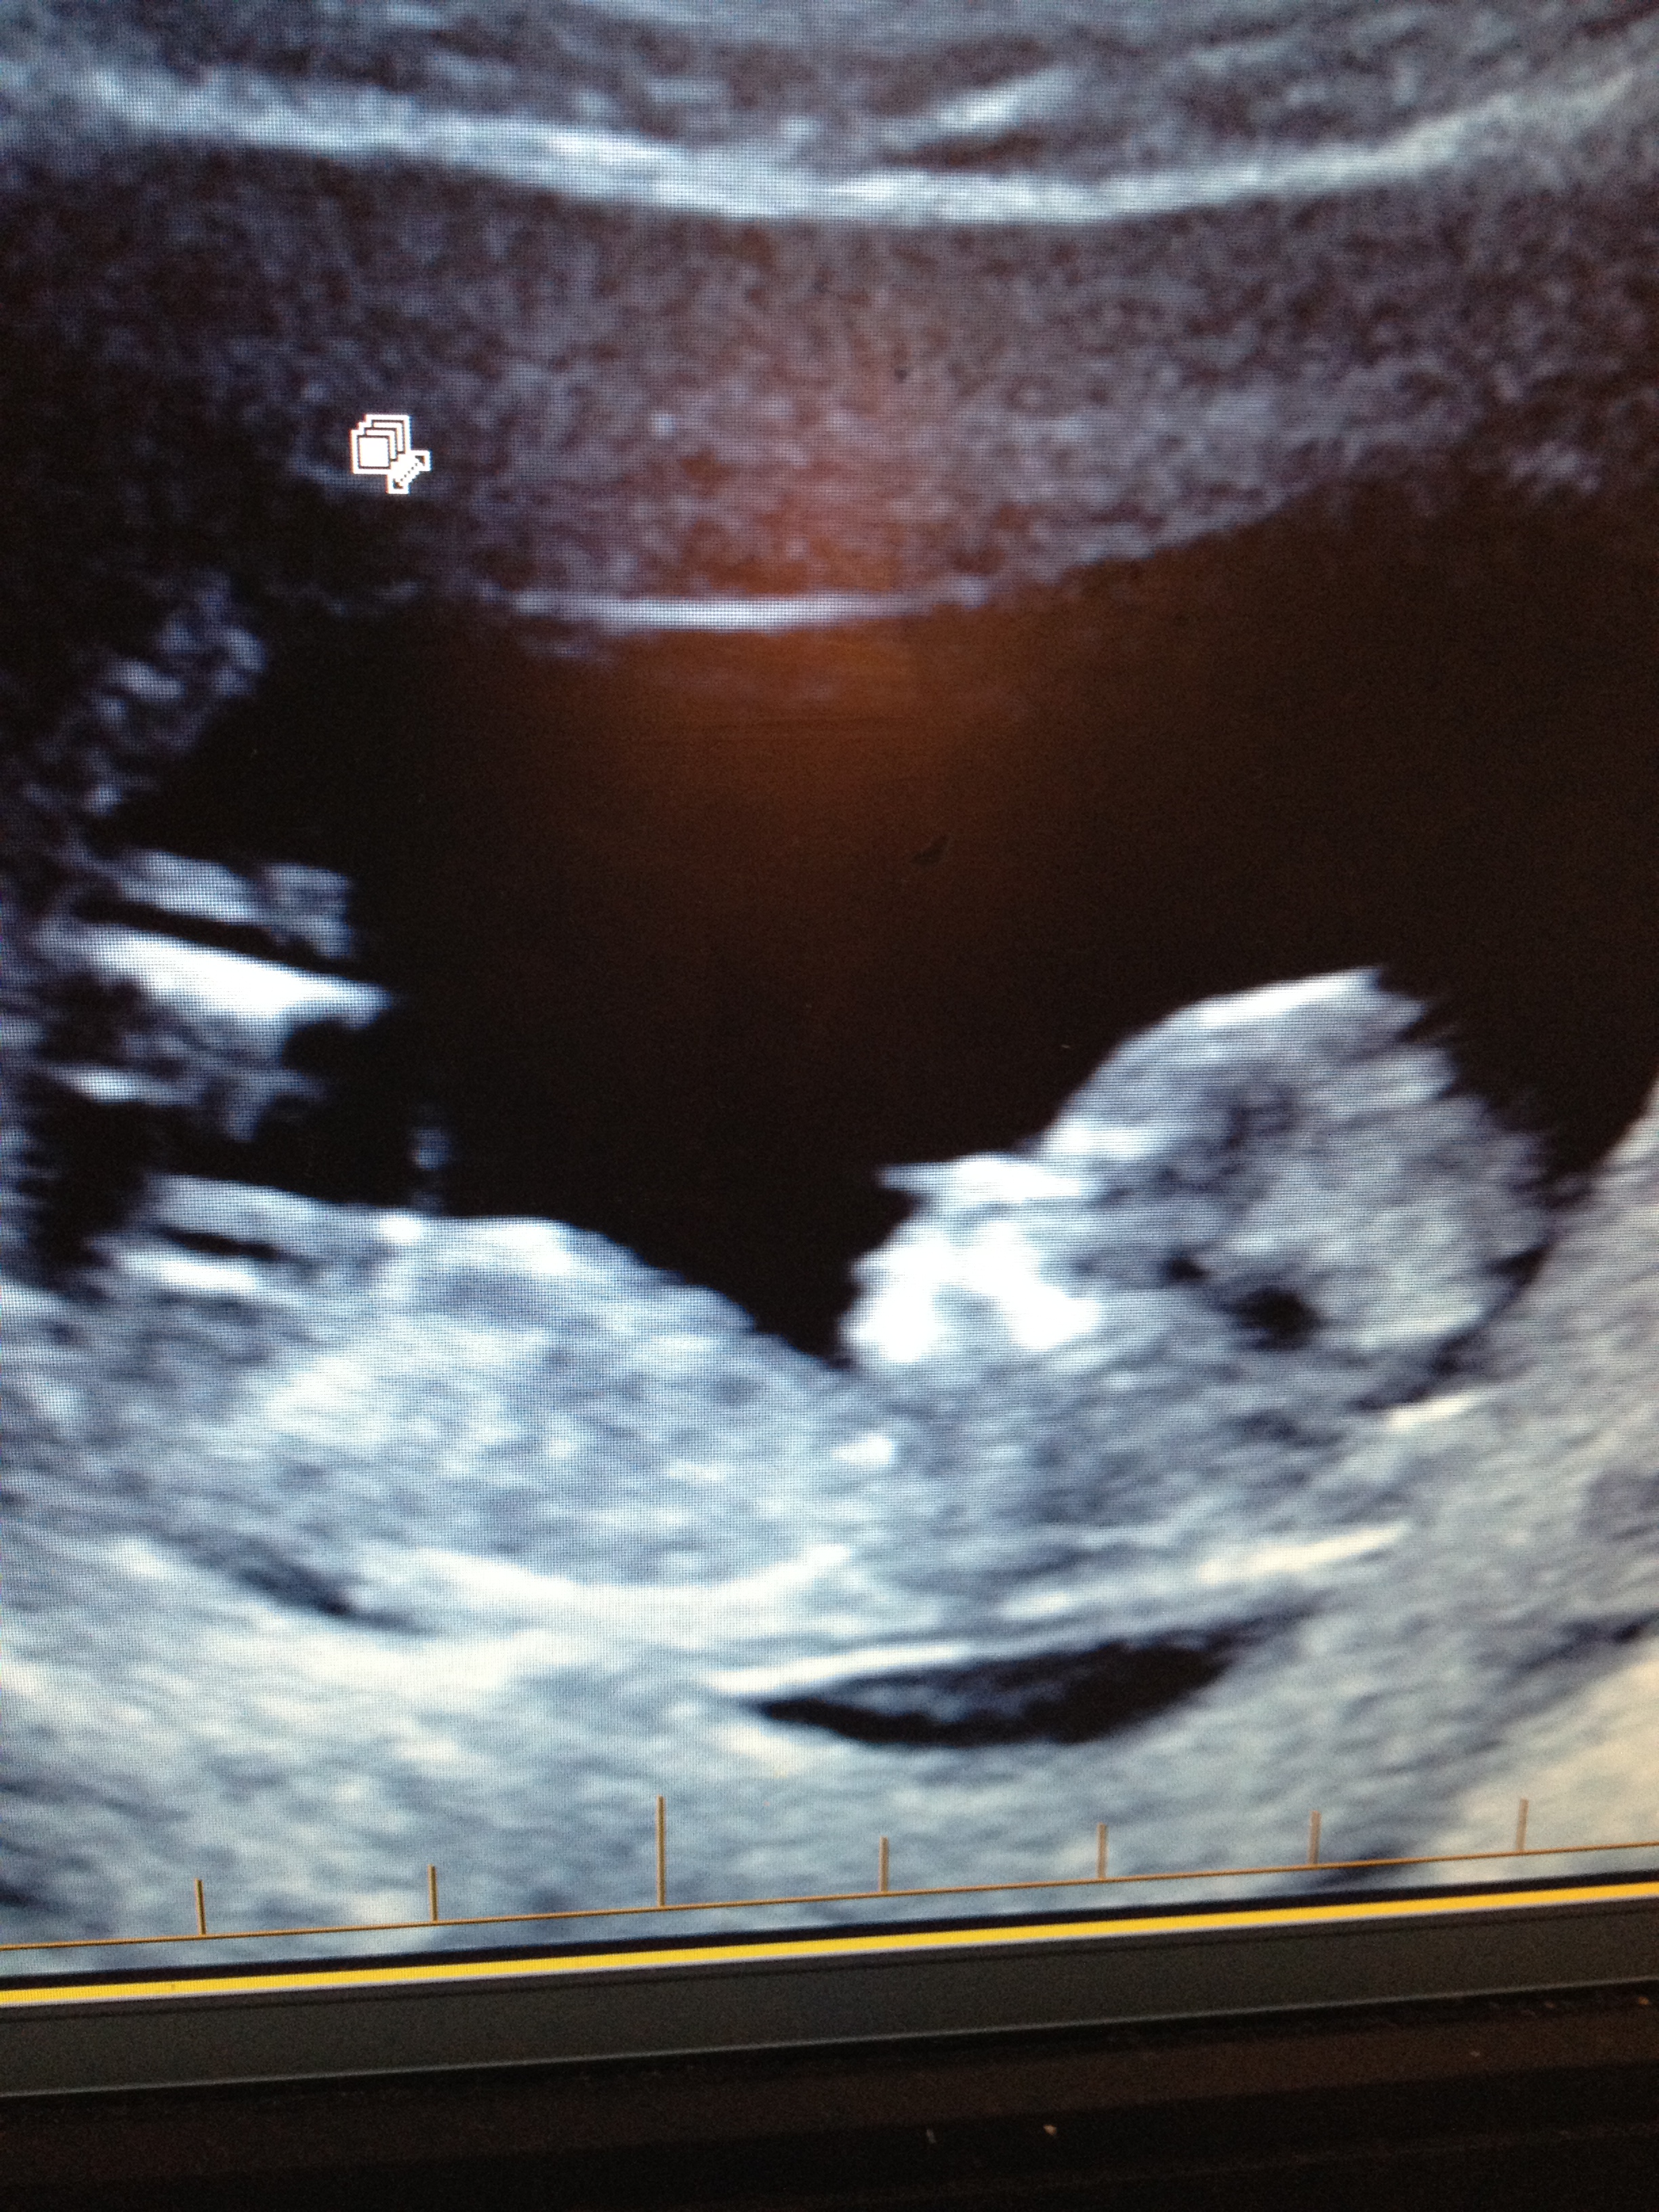

Not 100%, but leaning boy. Fx I'm wrong. xo

:DD: nub looks long and flat! :) x

most of the pictures look girly to me! one of them I wasn't sure about, but if we go on angle, I think it would be more obviously boy by now if it were a boy. So, guessing girl

Anymore guesses? I'm pretty convinced it's my girl. My boys were all angled up way more at 12 weeks.

All the pics look girly except third picture that says 'spine' kind of throws me. I 'think' it is just that baby is lower down and bum looks raised a bit that the nub doesn't look quite so flat. Anyone else agree?

Also pic one looks like little girl labia? Would it be to early to see this?